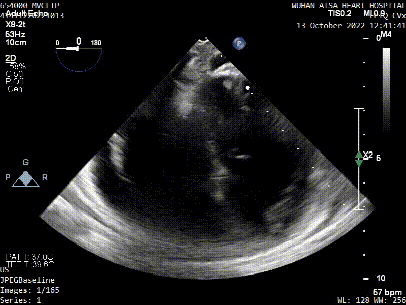

患者全身麻醉消毒铺巾后,建立右侧股静脉入路,在经食道超声指导下房间隔穿刺。根据要求,房间隔穿刺高度至少需要4.0cm,患者本身的解剖结构,左房和右房都比较小,如果选取卵圆窝靠后,靠中上的位置穿刺点高度只有2.6cm,是无法完成整个手术操作的,那么想要在安全的前提下获得更充分的房间隔穿刺高度,考虑选择在房间隔肌部穿刺,采用穿刺针的内芯,PCI导丝,甚至电刀穿刺的方式,都无法突破房间隔。患者的卵圆窝松弛,肌部又硬,苏晞院长团队决定在肌部与膜部交界的位置穿刺,经过精细调整,精准定位,最终以3.64cm的极限高度突破房间隔,而后将MitraClip™可操控导引导管(SGC)送入左心房。

将MitraClip™XTR送入左房,由于左房太小,在达到骑跨过程中反复推进回撤CDS和稳定器,同时旋转SGC,达到骑跨的同时,保证Clip头端游离,且SGC在左房有深度。旋转M,同时顺时针往后旋转SGC借高度,使Clip垂直二尖瓣环平面,由于穿刺高度不够,Clip直接进入左室,这意味着操作要十分小心,左室组织复杂,稍有不慎将会造成组织损伤。使用A/P Konb中“A”旋钮借高度。确认垂直后,直接在左室打开Clip,3D外科视角,逆时针旋转使Clip夹臂处于11点-5点方向,回拉稳定器,使Clip处于3区脱垂区域,用“+/-”Knob中的“-”旋钮,使Clip更往后叶的同时增加操作高度,抓捕脱垂的瓣叶,关紧Clip后,反流从4+降低至0级,平均跨瓣压差2mmHg,左右肺静脉逆流均改善。前后叶活动度降低,后叶插入长度9mm,前叶插入12mm, 确认稳定性后释放Clip。释放后,即刻效果十分满意,手术圆满结束。